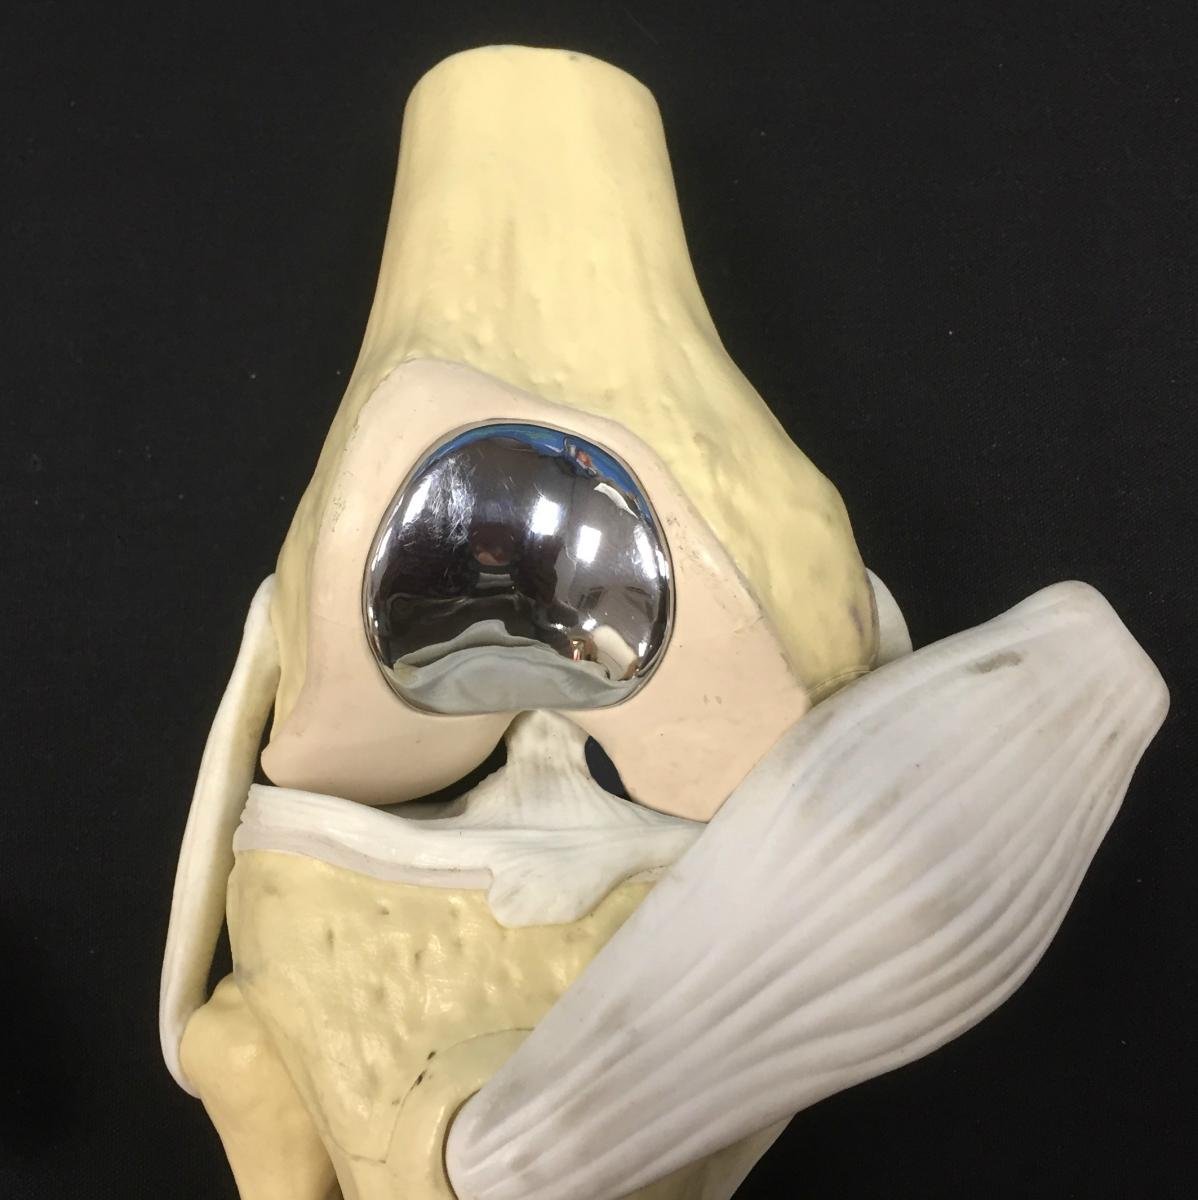

The term 'resurfacing' is often used to refer to these types of smaller implants because they only replace the damaged area of joint cartilage. It does not involve the removal of a bone block as in the total or partial knee replacement; instead the damaged cartilage is removed and a shallow bone bed is created to place the implant into the surface. In knee surgery these implants are usually used on the surface of the condyles (end of the femur) or for the damaged kneecap and groove in which the kneecap (patella) runs. Because only the surface of the joint is replaced the rest of the structures in the knee, namely the menisci and cruciate ligaments are left intact. This allows patients to resume normal activity levels and even return to sports after the appropriate rehabilitation has been completed. This image shows a model of the knee, with the patella and its tendon pulled over the side to show where a metal trochlear (groove) implant has been positioned with its stem and the rear of the implant fixed in place with a special cement. A matching polyethylene (medical plastic) implant would similarly be placed at the back of the patella.

Such resurfacing procedures are helpful in the younger and active patient who has perhaps had a sporting injury to the knee that has damaged the joint surfaces of the kneecap and groove but where the articulation between tibia and femur is still good and all the knee ligaments are intact. Surface replacements can later be converted to a total joint replacement as the majority of the bone is left intact.